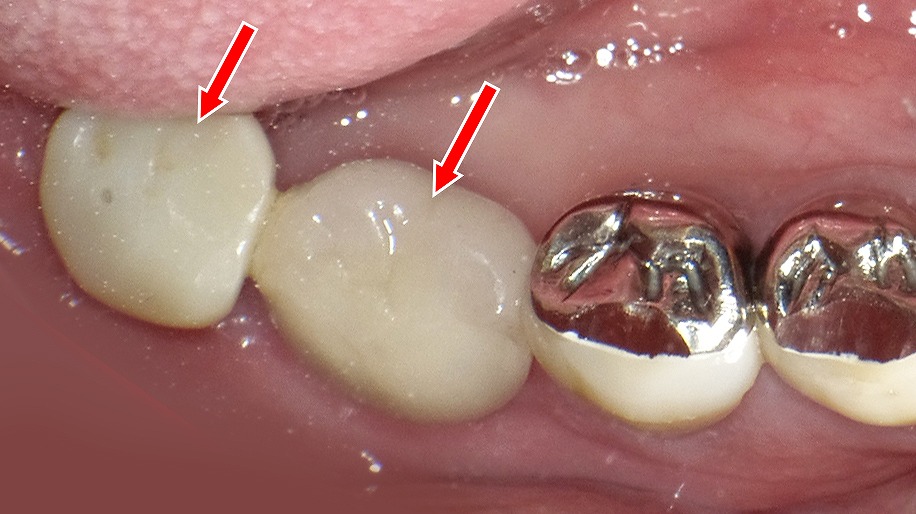

ブリッジを支える支台歯に、重度歯周病による歯槽骨吸収と歯の動揺が認められる症例です(赤矢印)。さらに、支台歯の一部には歯根破折が確認されており、これが痛みや違和感、噛んだときの不快症状の原因となっています。

ブリッジは複数の歯で力を支える治療法のため、歯周病が進行すると負担が集中し、炎症の悪化や歯根破折を引き起こすリスクが高まります。痛みが出た場合は、単なる噛み合わせの問題だけでなく、歯周組織や歯根の状態を含めた精密な診断が重要です。